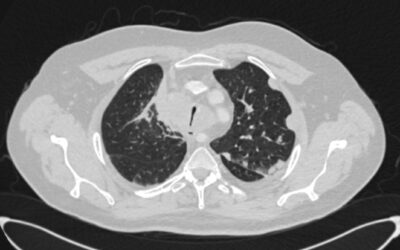

პაციენტი, 41 წლის მამაკაცი, 2015 წლის ოქტომბერში დაესვა მარჯვენა ფილტვის ბრტყელუჯრედოვანი გაურქოვანებელი კარცინომის დიაგნოზი. მიუხედავად ქიმიოთერაპიისა და რადიაციული თერაპიისა, პაციენტის კლინიკო-ლაბორატორიული და რადიოლოგიური მონაცემები გაუარესდა. გაუჩნდა სტრიდორული...